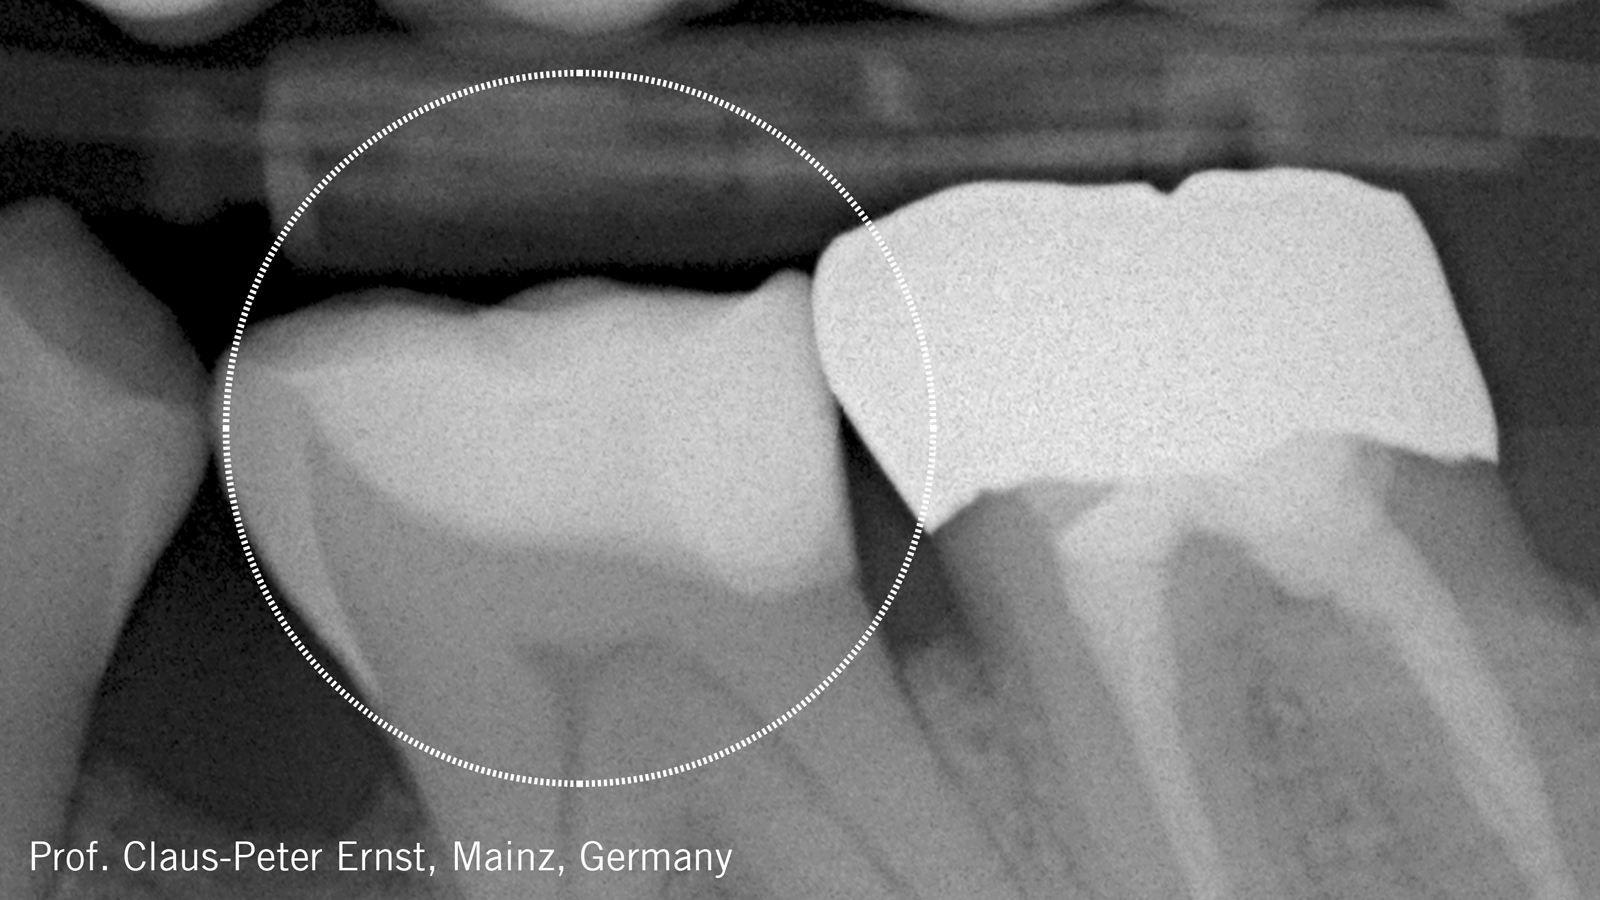

Este caso do Prof. Nicola Scotti (Universidade de Turim, Itália) mostra a eficiência e excelente estética de uma restauração com Charisma Diamond ONE

Cárie secundária na restauração de amálgama do dente 26.

Paciente do sexo masculino, 59 anos, apresentando cárie secundária na restauração de amálgama do dente 26.